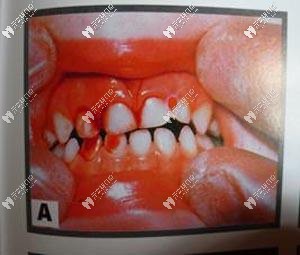

牙震蕩和磕掉牙一樣,都屬于牙齒受到外力作用出現(xiàn)的損傷。不同的是,牙齒磕掉了,你肯定一邊哭一邊沖去醫(yī)院,然而如果是碰上了牙震蕩,表面上看牙齒本身一點(diǎn)毛病都沒有,躺槍的是牙髓神經(jīng)和牙周組織,要說癥狀,可能會(huì)出現(xiàn)牙齒輕微的叩痛、牙齦邊緣出血等。

輕度牙震蕩表現(xiàn):從外觀來看一般沒有太多異樣,咬合時(shí)有輕微不適感。? ??

重度牙震蕩表現(xiàn):牙齒有輕度或中度的松動(dòng),咬合時(shí)有明顯的疼痛感,牙冠出現(xiàn)粉紅色。? ??